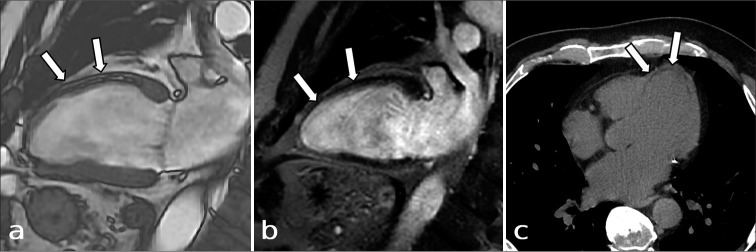

Abstract Image